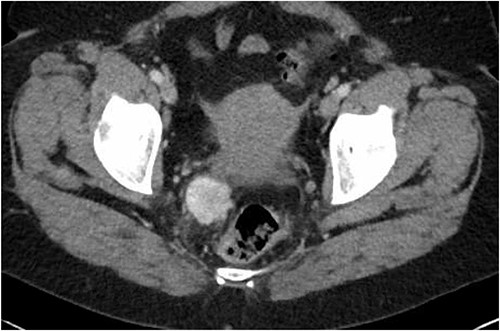

This is the case of a healthy 66-year-old female, referred to a colorectal surgery center for a slow-progressing pararectal mass of 14 years. This incidental finding had since been followed by computed tomography (CT). The mass had progressed from 19 mm to 34 mm (Fig. 1). She had a single dysplastic rectal polyp resected 2 years earlier, but no history of malignancy. She was asymptomatic, apart from a recently growing pain in her right groin.

Latest CT evaluation prior to consultation, showing a right pararectal hypervascular mass.